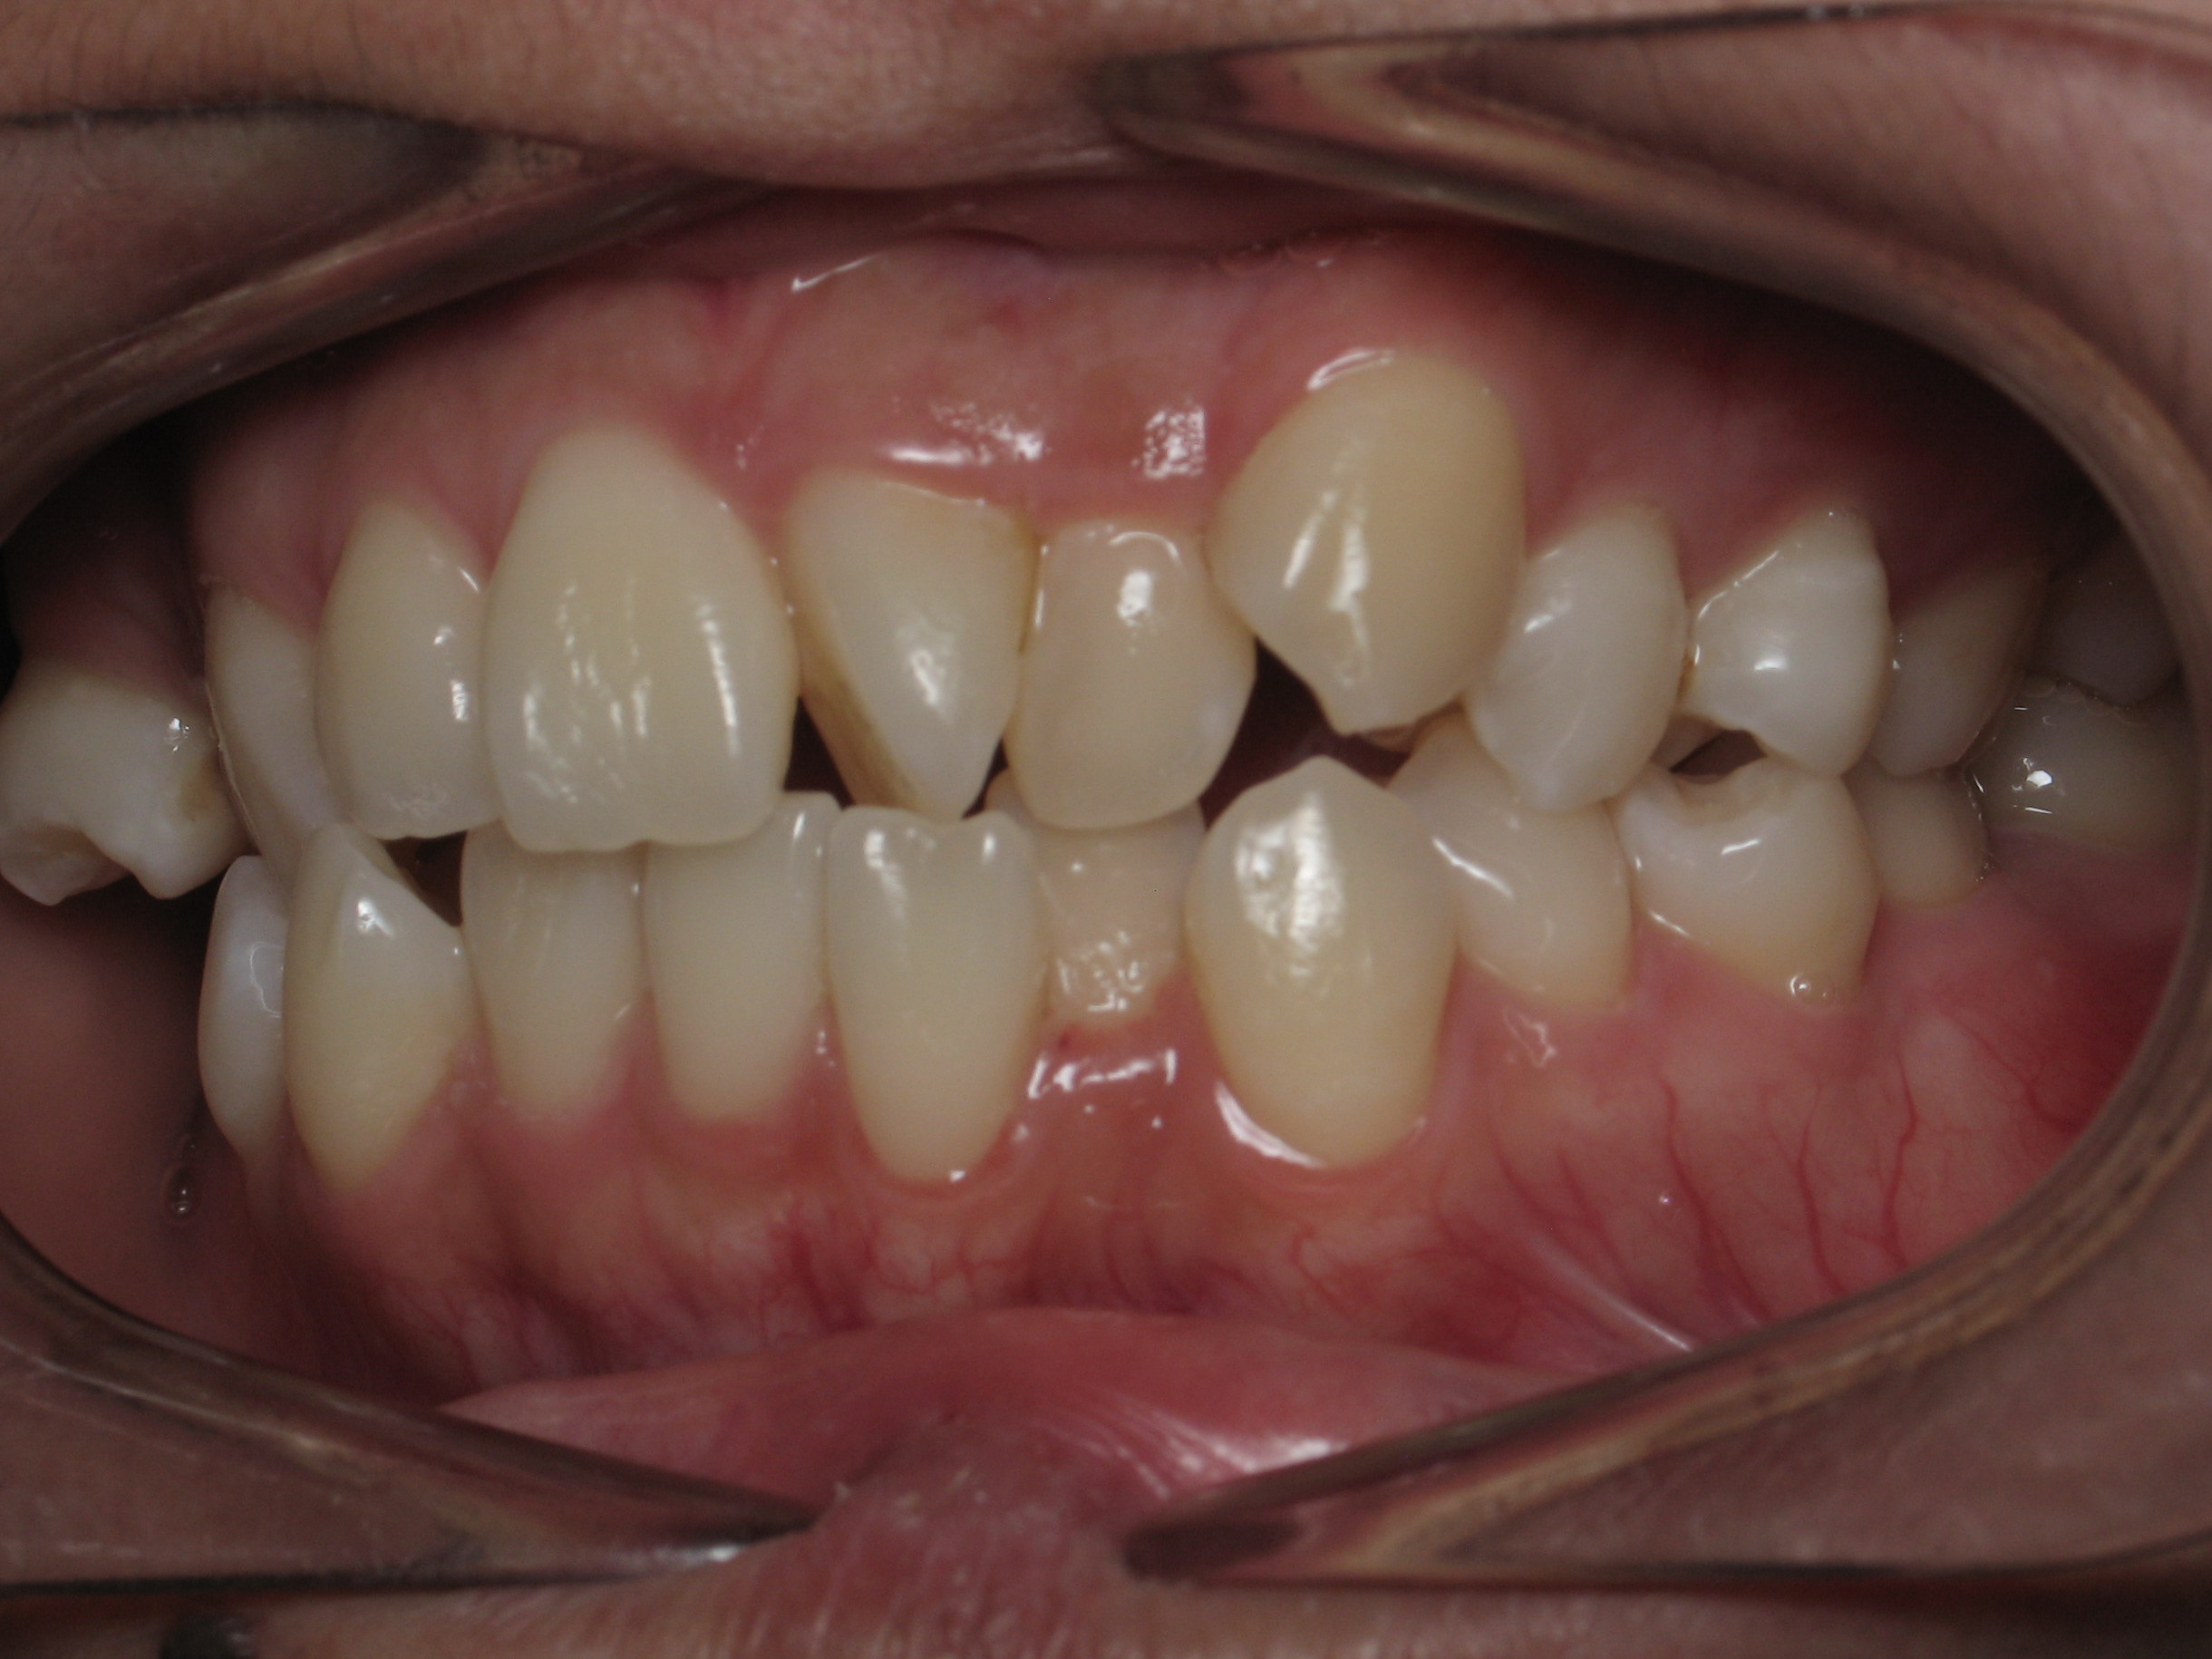

Smile Gallery